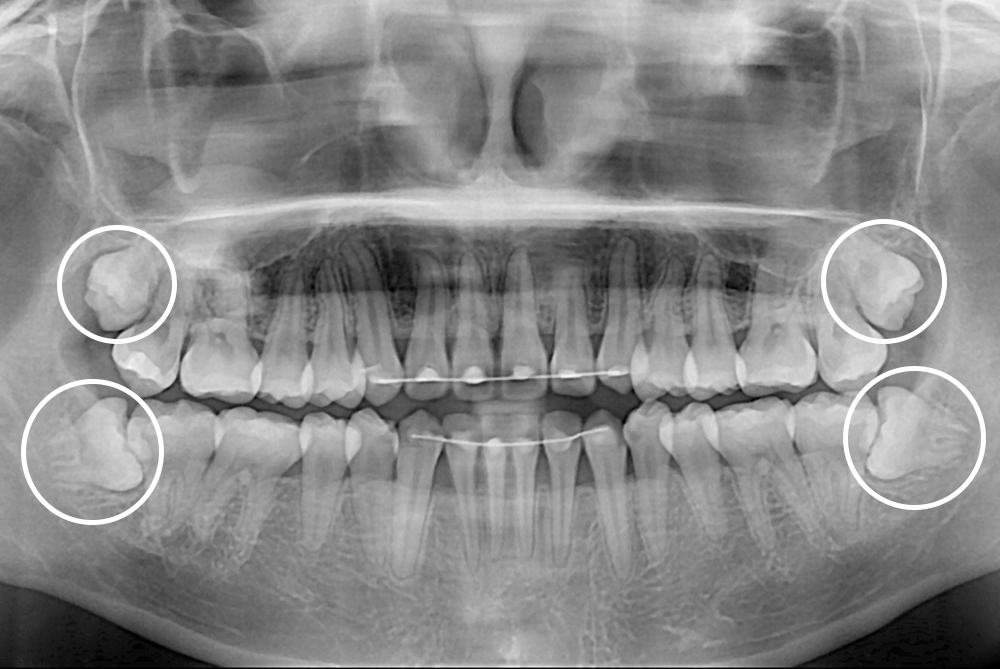

[사랑니] 매복 사랑니 발치

치료전 : 2018-02-12

세종치과는 구강악안면외과학 박사이신 원장님이 발치하는 치과입니다.